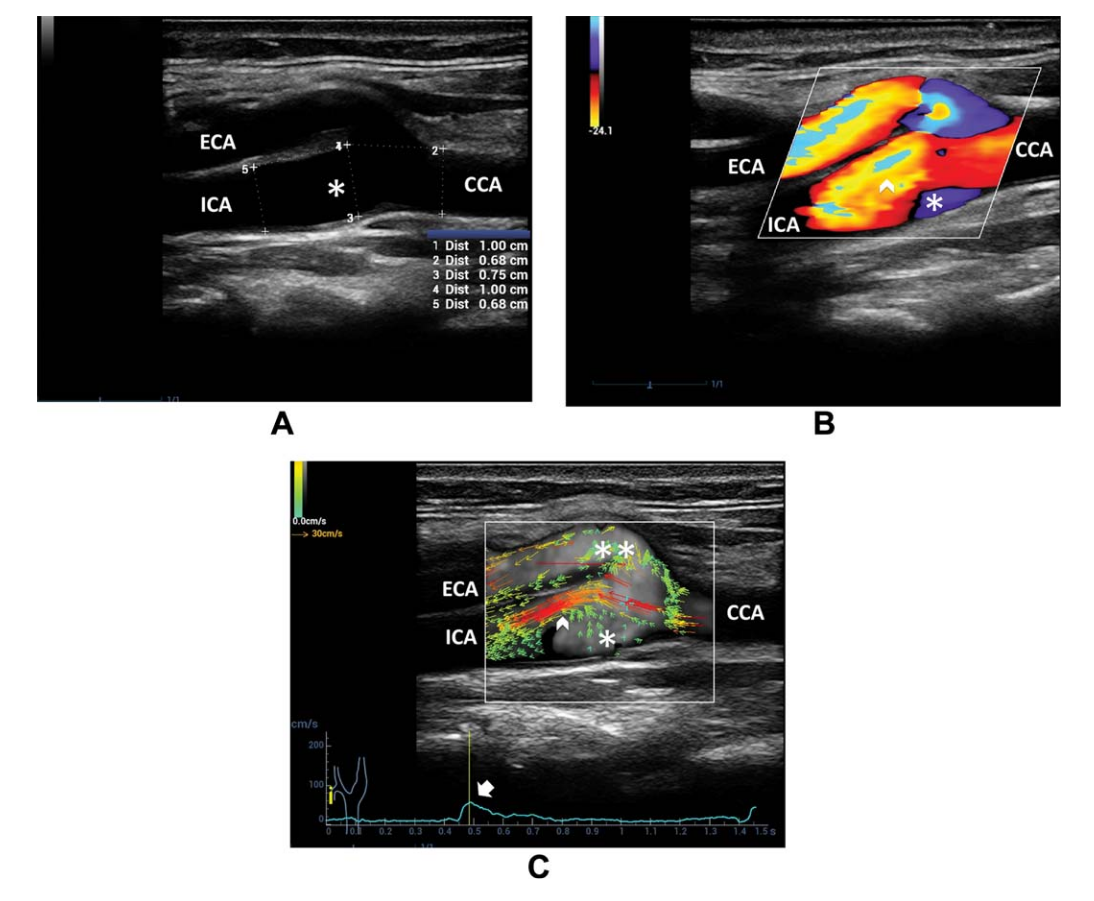

Figure 1. Pulsed-Wave Doppler in the carotid common artery (CCA)

Figure 8. A, B-mode US of the carotid bifurcation shows vessel diameter enlargement from the CCA to ICA sinus B, Color Doppler imaging depicts the high-velocity flow in the ICA sinus near the flow divider (arrowhead) and recirculation on the opposite side (asterisk). C, Vector flow imaging shows the high-velocity red vectors near the ICA flow divider (arrowhead) and multidirectional low-velocity green vectors on the opposite side (single asterisk) and at the external carotid artery (ECA) entrance (double asterisks), starting at the systolic peak (arrow on the velocity-versus-time curve)